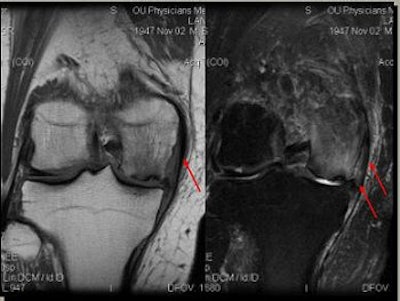

![]() |

| Edema in MCL from osteochondritis dissecans (OCD) and chrondomalacia. |